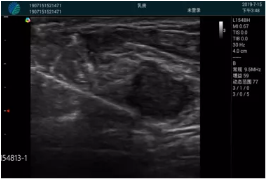

腺體內(nèi)部清晰顯示一低回聲塊影,形態(tài)不規(guī)則,邊界模糊,邊緣呈毛刺狀,內(nèi)部見砂礫樣鈣化

M20引導(dǎo)下穿刺活檢術(shù)